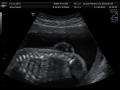

Three-dimensional ultrasound image of the fetal spine at 21 weeks of pregnancy

-

Ultrasound view of the fetal spine at 21 weeks of pregnancy. In the longitudinal scan a lumbar myelomeningocele is seen.

Open spina bifida can usually be detected during pregnancy by fetal ultrasound. Increased levels of maternal serum alpha-fetoprotein (MSAFP) should be followed up by two tests - an ultrasound of the fetal spine and amniocentesis of the mother's amniotic fluid (to test for alpha-fetoprotein and acetylcholinesterase). AFP tests are now mandated by some state laws (including California). and failure to provide them can have legal ramifications. In one case a man born with spina bifida was awarded a $2 million settlement after court found his mother's OBGYN negligent for not performing these tests.[62] Spina bifida may be associated with other malformations as in dysmorphic syndromes, often resulting in spontaneous miscarriage. In the majority of cases, though, spina bifida is an isolated malformation.

Genetic counseling and further genetic testing, such as amniocentesis, may be offered during the pregnancy, as some neural tube defects are associated with genetic disorders such as trisomy 18. Ultrasound screening for spina bifida is partly responsible for the decline in new cases, because many pregnancies are terminated out of fear that a newborn might have a poor future quality of life. With modern medical care, the quality of life of patients has greatly improved.[54]